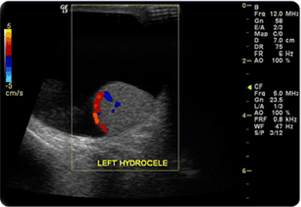

음낭수종(Hydrocele)이란?

음낭수종은 고환을 둘러싸고 있는 초막에 액체가 고이는 질환으로 고환과 초막사이 액체가 증가해 수류가 형성되면서 음낭이 부풀어 오르게 되는 증상으로, 신생아 또는 생후 수개월 정도에서 나타나는 것이 일반적이고, 30~40대 이후의 성인에서도 흔하게 나타날 수 있습니다.

사진